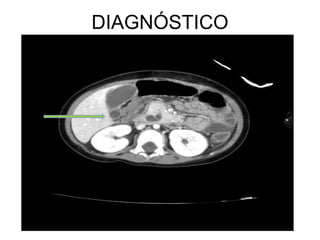

DIAGNÓSTICO